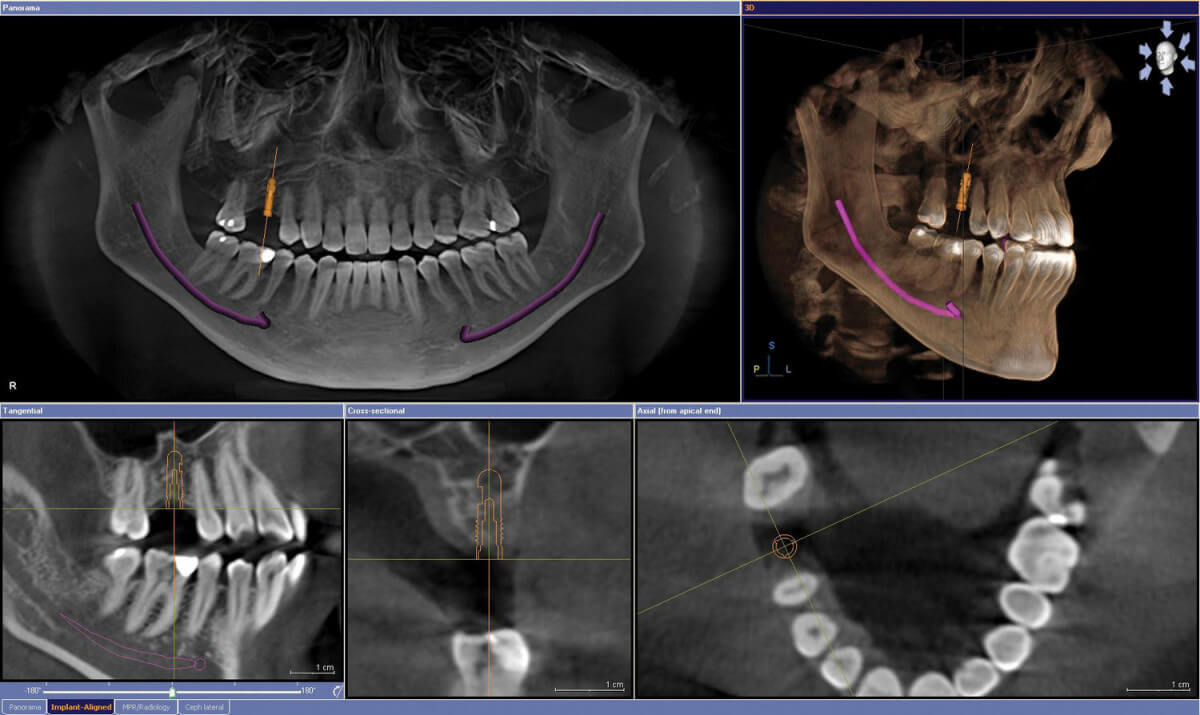

• Имплантологи: энэ нь шүдний мэс заслын нэг чиглэл ба имплант суулгах шинжлэх ухааныг хэлнэ. Имплант суулгахад зарим хүний ясны зузааныг зөвхөн тэмтэрч үзэн, зузааныг баримжаалан хийдэг ба, СТ зураг авсанаар, тухайн хүний ясны зузааныг 0,01 мм-ийн нарийвчлалтайгаар хэмжиж имплант төлөвлөж болно. Хөтөчтэйимплант хийхэд, СТ зураг зайлшгүй шаардлагатай болдог.

Зураг дээр СТ зураг ба дижитал загвараа хөтөч хийдэг програмд ачаалан ирээдүйн имплантаа дижиталаар байрлуулж, хөтөч бэлдэх явцыг харуулж байна.